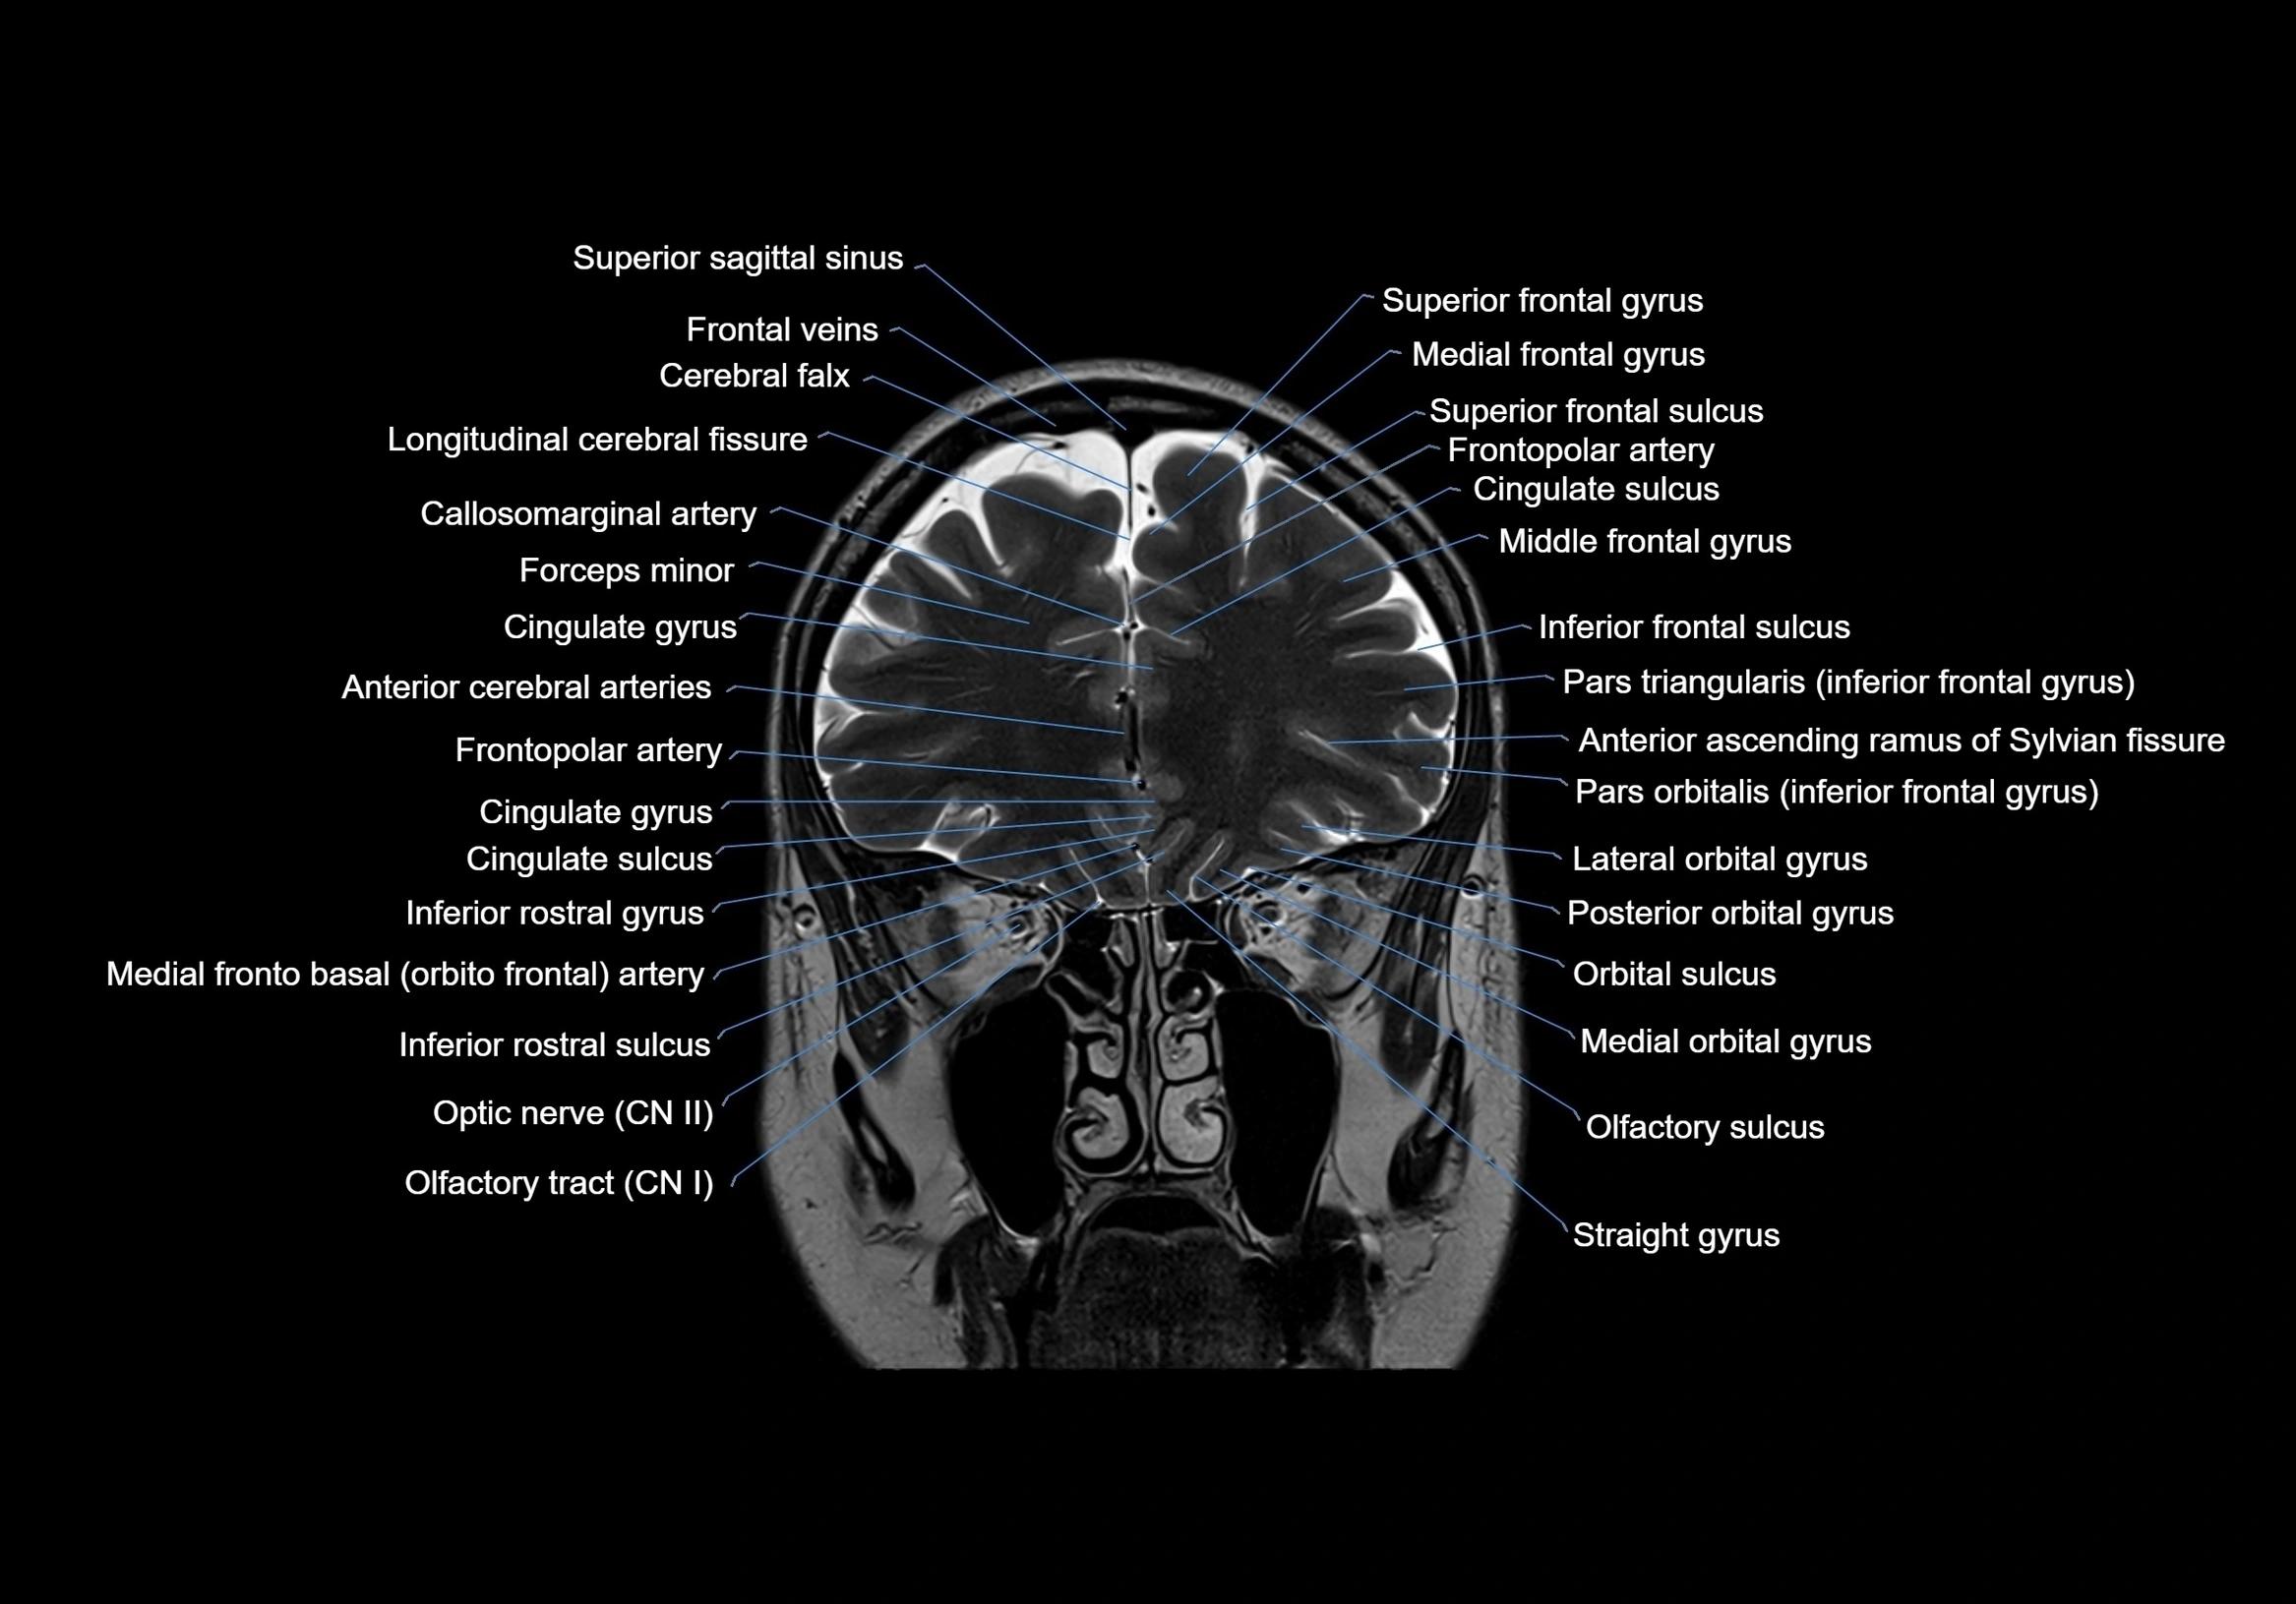

MRI images